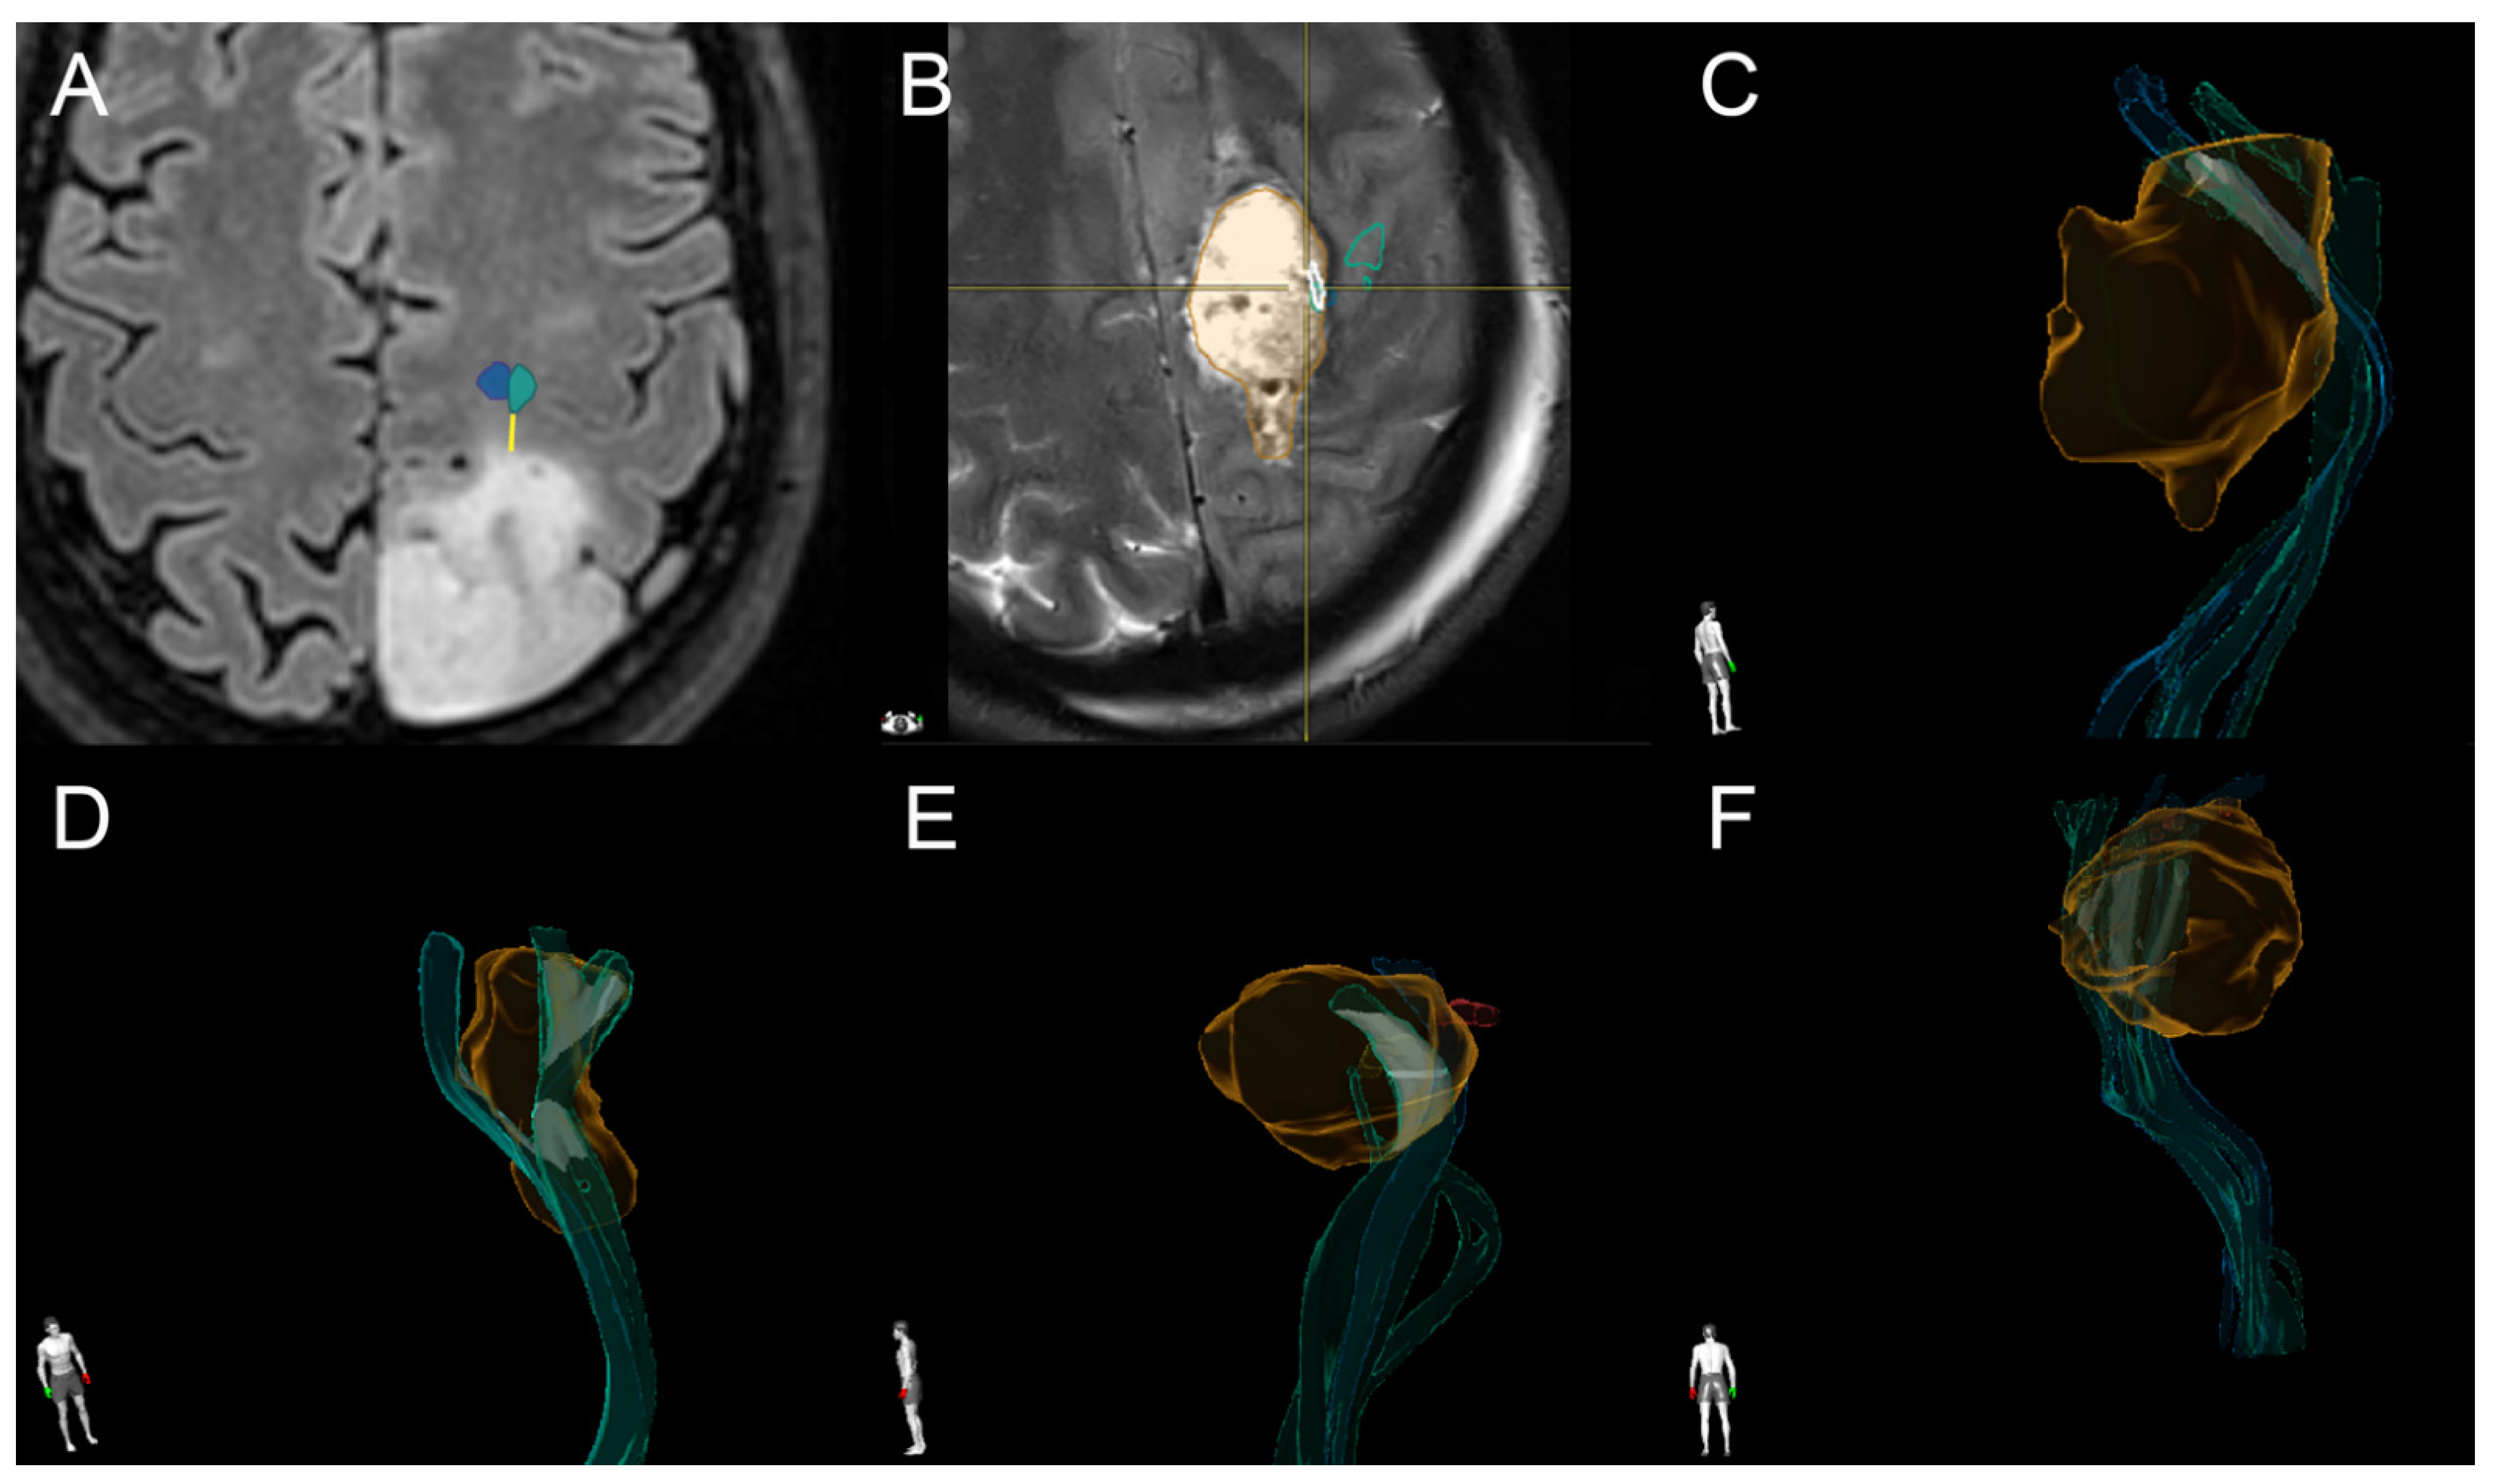

2.5. Tractography

2.6. IOM

3.2. Analysis of TTD and TRD